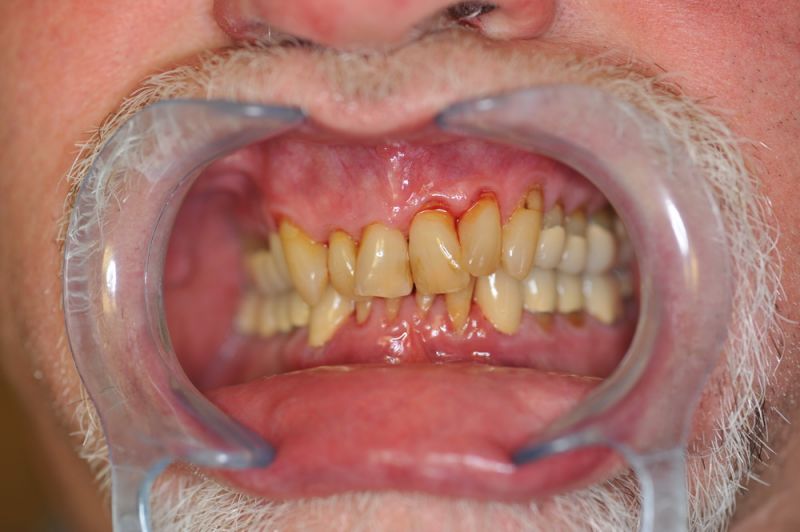

80 jähriger Patient aus Kiel erhält die beiden letzten Rekonstruktionen. Behandlung abgeschlossen

Der Patient erhält die beiden letzten Kronen zur Einstellung der dynamischen Okklusion.

Die funktionstherapeutische Behandlung ist damit abgeschlossen. Der Patient ist vollkommen beschwerdefrei. Beschwerdelevel: "0".

Es erfolgt engmaschiger vierteljährlicher Recall mit Überprüfung der statischen und dynamischen Okklusion.